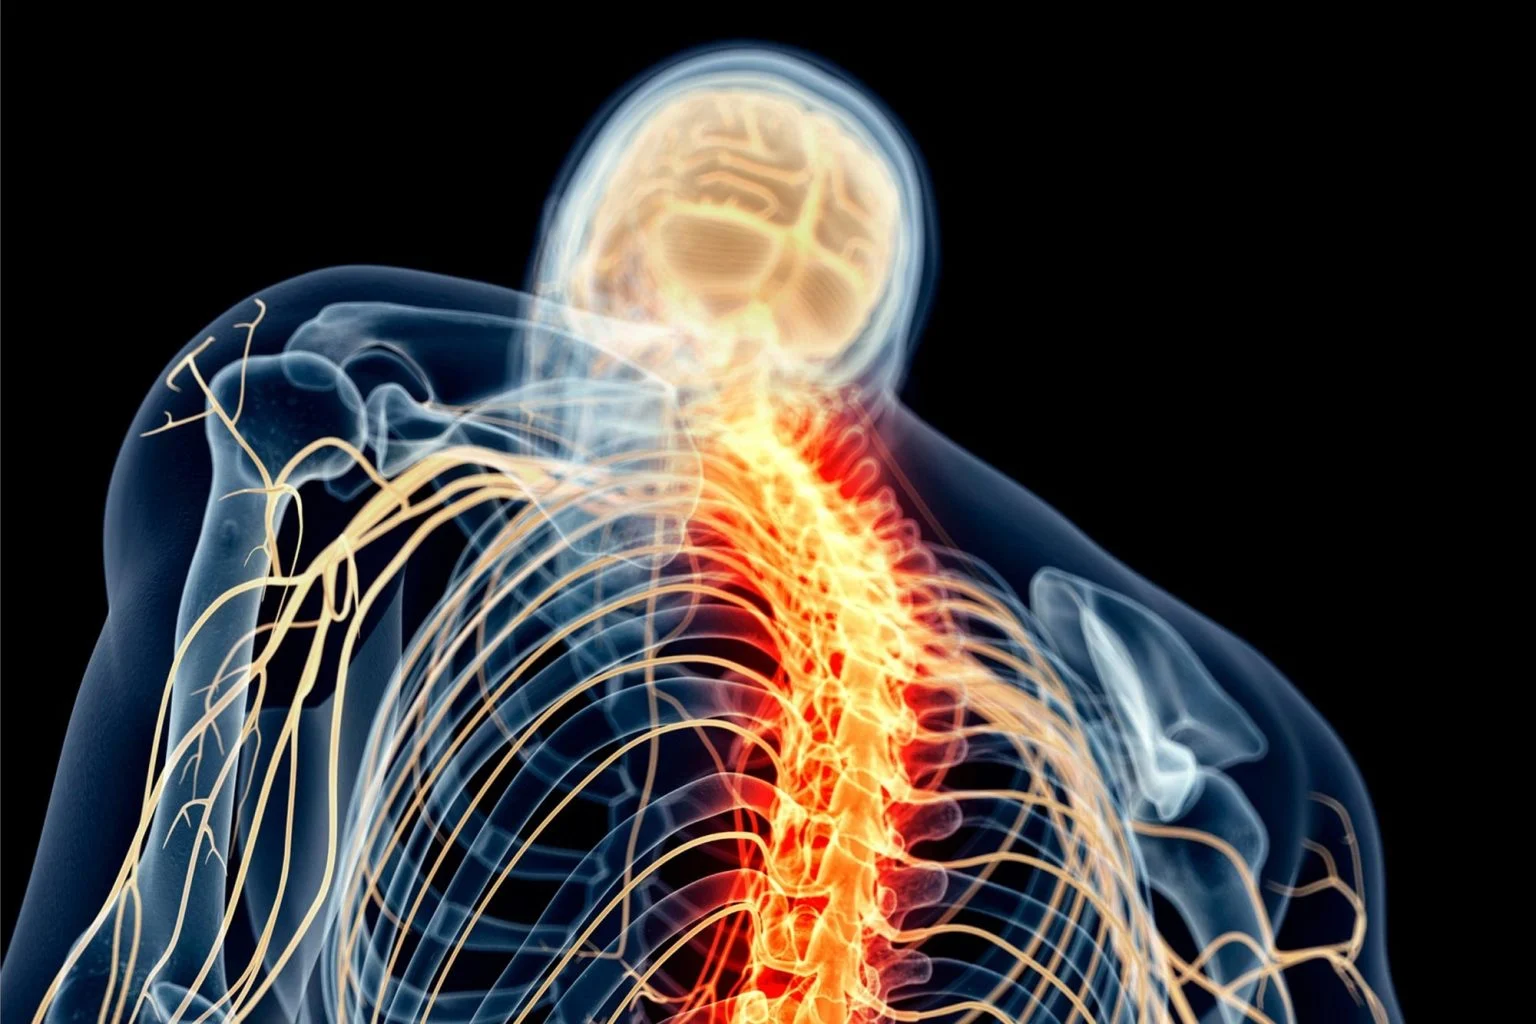

كشف باحثون في مركز «سيدارز-سيناي» الطبي بأمريكا عن وظيفة بيولوجية خفية غير معروفة سابقاً لخلايا الدماغ، من شأنها إحداث ثورة في علاج إصابات الحبل الشوكي، والسكتة الدماغية، والأمراض العصبية المزمنة مثل التصلب المتعدد. وأظهرت الدراسة، أن نوعاً خاصاً من الخلايا النجمية يقع بعيداً عن موقع الإصابة، أطلق عليه العلماء اسم «الخلايا النجمية البعيدة عن الآفة»، يلعب دوراً حاسماً في عملية ترميم الأنسجة عبر إرسال إشارات متطورة للجهاز المناعي.

وأوضح الفريق البحثي بقيادة عالم الأعصاب «جوشوا بوردا» أن هذه الخلايا تفرز بروتيناً يسمى «CCN1»، يعمل كمحفز حيوي للخلايا الدبقية الصغيرة، حيث يوجهها لتغيير عملية التمثيل الغذائي لديها لتتمكن من هضم وإزالة الحطام الدهني الناتج عن الألياف العصبية المقطوعة. وأثبتت التجارب التي أجريت على فئران المختبر وعينات بشرية أن غياب هذا البروتين يؤدي إلى تراكم النفايات العصبية وزيادة الالتهابات، ما يعطل عملية الشفاء التلقائي للأنسجة.

ويفتح هذا الاكتشاف آفاقاً علاجية جديدة تعتمد على تسخير آلية عمل بروتين «CCN1» لتعزيز التعافي العصبي والحد من الالتهابات المزمنة.

وظيفة «خفية» لخلايا الدماغ تسرع علاج الحبل الشوكي